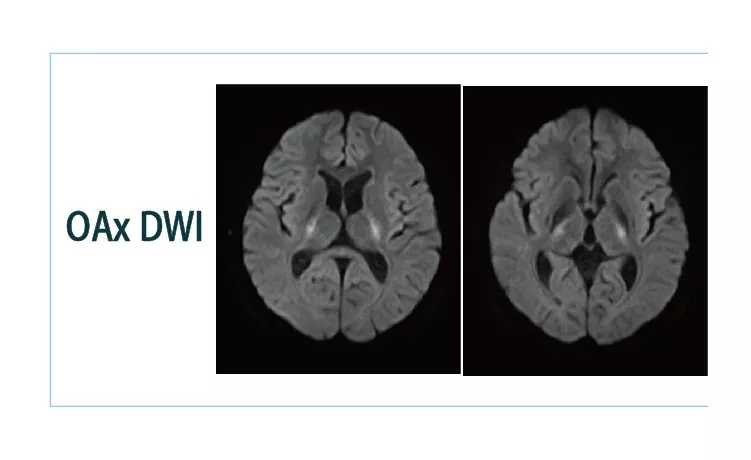

1544579634898245.jpg1544579646797662.jpg